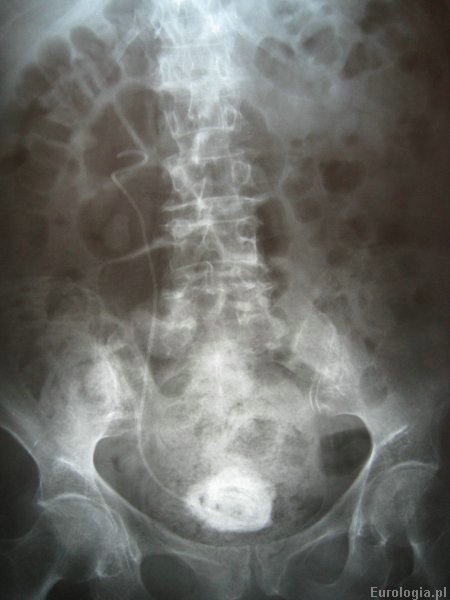

W chwili przyjęcia pacjentka w złym stanie ogólnym, gorączkująca, odwodniona. W badaniach laboratoryjnych stwierdzono wysoką leukocytozę i podwyższone parametry nerkowe. Ze względu na roponercze prawostronne stwierdzone w USG jamy brzusznej zdecydowano o założeniu nefrostomii. Z założonej przetoki nerkowej uzyskano 200 ml ropy, którą wysłano na posiew. W wykonanym zdjęciu przeglądowym nerek i pęcherza stwierdzono prawidłowo ustawiony cewnik DJ w moczowodzie po stronie prawej z masywnym zwapnieniem końca pęcherzowego cewnika.

Fot. RTG przeglądowe nerek i pęcherza moczowego z widocznym cewnikiem DJ w prawym moczowodzie i kamieniem moczowym na końcu pęcherzowym cewnika.